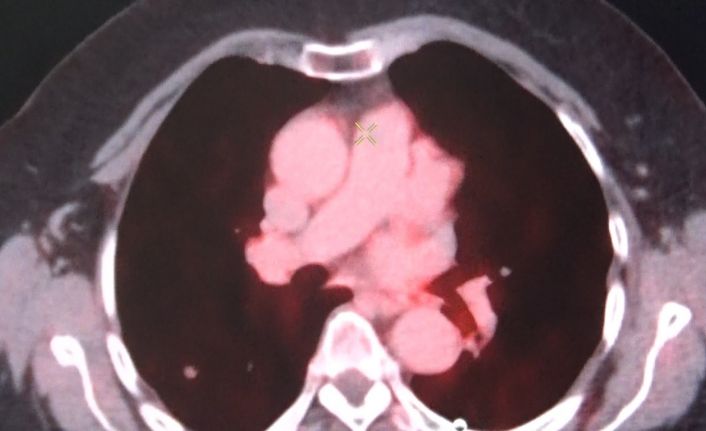

Diyarbakır Gazi Yaşargil Eğitim ve Araştırma Hastanesinde 2010 yılından bu yana hizmet veren Nükleer Tıp Bölümünde birçok hasta radyoaktif tedavisiyle şifa buluyor. Son nükleer tıp teknolojileriyle her türlü sintigrafik görüntülemenin yapıldığı bölümde, kalpten akciğere, karaciğerden kemik ve böbreğe kadar geniş bir alanda teşhis için SPECT/CT, SPECT, PET/CT ve FAPI cihazları kullanılıyor. Bölgenin en büyük etkin nükleer tıp merkezlerinden olan Gazi Yaşaragil Eğitim Hastanesinde 3 doçent doktor ve 5 uzman doktor ile Nükleer Tıp Bölümü hizmet veriyor. Nükleer Tıp Bölümünün sadece sintigrafik görüntülemeden ibaret olmadığını belirten Nükleer Tıp Uzmanı Doç. Dr. Halil Kömek, hastalığın yarısı oranında tedavi ile ilgilenen bir bilim dalı olduğunu söyledi. Kömek, “FDG PET/CT ile onkolojik tüm vücut görüntüleme yapan cihazlarımız mevcut. Prostat kanserleri için 68Ga-PSMA, nöroendokrin tümörleri görüntülemesi için 68Ga (Galyum68)-Dotatate ve ülkemizde birkaç merkezde uygulanan TİTCK (Türkiye İlaç ve Tıbbi Cihaz Kurumu) onaylı olduğumuz FAPI (fibroblast aktivasyon protein inhibitörü) ile kolorektal ve gastointestinal kanserlerinin periton yayılımlarında kullandığımız FAPI görüntülemesi yapmaktayız” dedi.

Hastanede yılda 6 bin hastanın tümör taraması amacıyla PET/BT görüntülemesinin yapıldığını söyleyen Kömek, “Hastanemizde ayrıca tiroid kanseri 300 hastaya İyot tedavisi yapılmakta. Yılda 400 hastaya da Lutesyum tedavileri, prostat kanserlerinin nöroendokrin tümörlerinin ya da ağrı palyasyonu amacıyla uygulanmaktadır. Açılımını yaparsak eğer, radyoaktif madde ile işaretlenmiş bir reseptör bağlacını hastanın vücuduna enjekte ediyoruz ve sadece tümörlü alanları tutup tedavi ediyor. Herhangi bir yan etkisi olmadan sadece tümöre spesifik reseptörlere bağlanarak tedavi edildiği için, hedeflenmiş radyoterapi dediğimiz sistemi kullanıyoruz. Bunun yanı sıra yılda yaklaşık 300 hastanın da hipertiroidi tedavisini yapmaktayız” şeklinde konuştu.